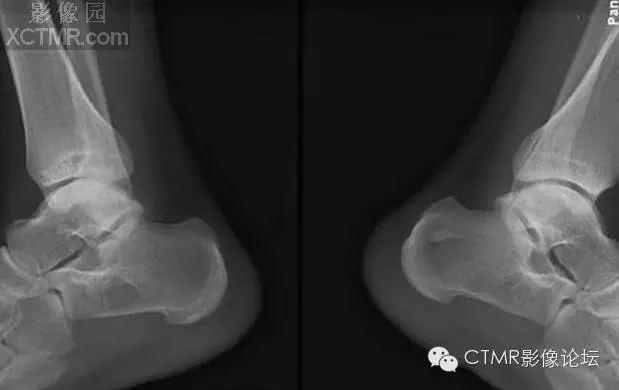

【X線表現(xiàn)】

1.跟骨竇的形成 跟骨示足弓的重要支點(diǎn),承受著來(lái)自自身及負(fù)荷的重量。為了適應(yīng)承受重量的力學(xué)需要,跟骨的結(jié)構(gòu)十分精密合理。其骨小梁的發(fā)育有三組:①自跟距關(guān)節(jié)后緣向后下方呈斜向走行;②沿跟骨下方分布;③自跟結(jié)節(jié)處向前方伸展。三組骨小梁間有一個(gè)類(lèi)三角形、圓形或橢圓形透亮區(qū),即跟骨竇。

2.跟骨竇的表現(xiàn) 觀察跟骨竇以側(cè)位平片為佳。其特點(diǎn)是位于跟骨前部中央,跟骨溝后方,尖端向上,足弓后上部,承受重量輕的特定位置。竇的基底與跟骨下緣平行。與竇基底相當(dāng)?shù)母窍戮壠べ|(zhì)密度高,呈致密帶狀或線狀。竇內(nèi)骨小梁稀少或缺如。邊緣清楚整齊,無(wú)硬化。大小1-3cm。竇內(nèi)有時(shí)可見(jiàn)營(yíng)養(yǎng)溝。多數(shù)為單側(cè),少數(shù)雙側(cè)對(duì)稱(chēng)發(fā)生。竇周骨質(zhì)正常。

骨髓竇是指松質(zhì)骨內(nèi)先天性骨小梁發(fā)育稀少,各組骨小梁間的骨小梁少或缺如,形成一空腔,內(nèi)含有骨髓,稱(chēng)為骨髓竇,為正常解剖變異。骨髓竇以跟骨最多見(jiàn),簡(jiǎn)稱(chēng)骨髓竇,其次見(jiàn)于股骨頸、股骨遠(yuǎn)端及髖臼上緣等處。X線表現(xiàn)邊緣清楚整齊,無(wú)硬化,大小1-3cm,病變區(qū)內(nèi)無(wú)鈣化,竇內(nèi)有時(shí)可見(jiàn)營(yíng)養(yǎng)溝。竇周骨質(zhì)正常。